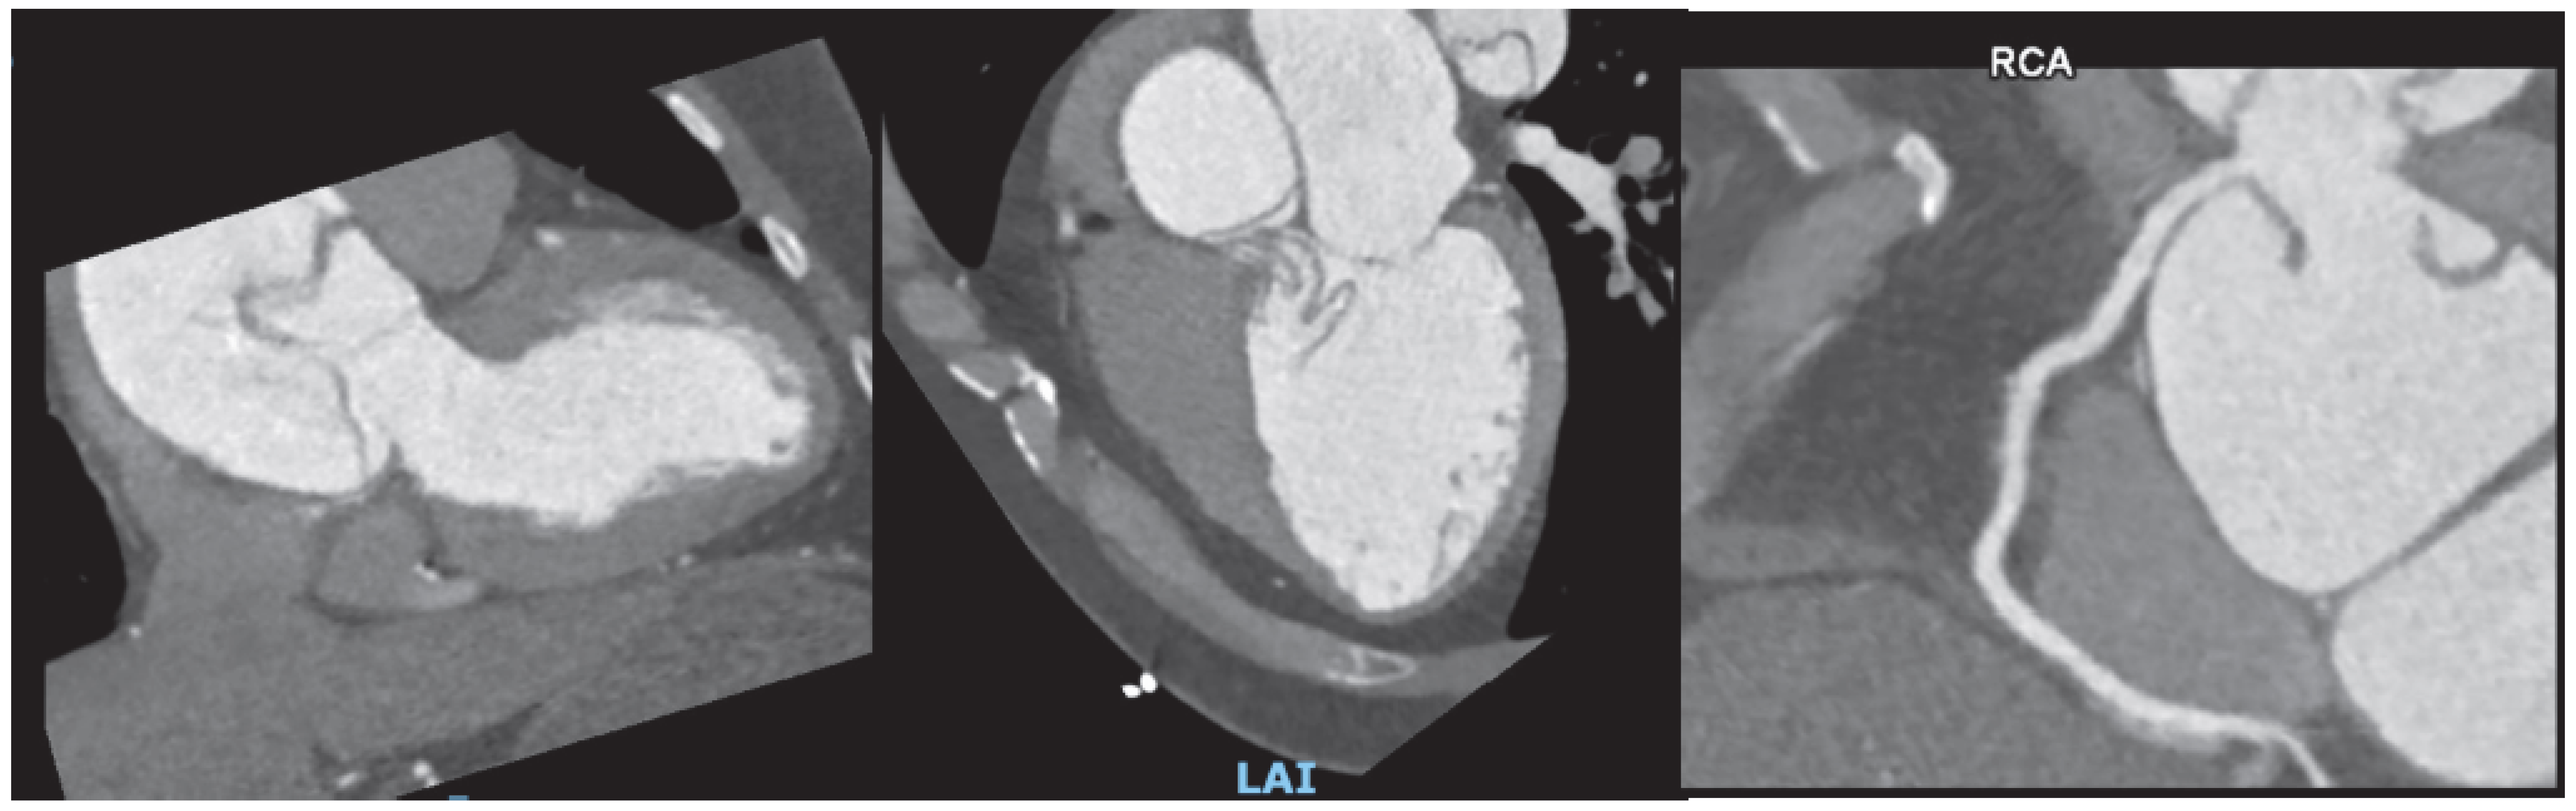

Furthermore, direct measurement of the aortic valve coaptation area defect can be achieved through planimetry at the leaflet tips. This technique also enables precise assessment of aortic regurgitation by examining valve closure during diastole. Prior to transcatheter valvular aortic replacement (TAVR), CCTA can offer precise measurements of not only the aortic annulus but of the entire aortic root and offers essential information in the assessment of vascular accesses [47] (Figure 6). The clinical impact of CT-based planning is supported by real-world evidence: Mylotte et al. reported that CT analysis frequently resulted in larger annular measurements than transesophageal echocardiography (TEE) alone, and that adherence to CT-based oversizing criteria was independently associated with a 21% lower incidence of paravalvular leak compared with TEE sizing (14% vs. 35%; p = 0.003) [48]. Similarly, in a prospective study of 266 patients, CT-based prosthesis sizing significantly reduced paravalvular leak rates (5.3% vs. 12.8%; p = 0.032) and in-hospital mortality (3.8% vs. 11.3%; p = 0.02) compared with sizing based on echocardiography and angiography [49]. Post-TAVR, cardiac CT is valuable in the evaluation of suspected prosthetic valve thrombosis, endocarditis, or structural deterioration, with characteristic findings such as hypoattenuated leaflet thickening (HALT) and reduced leaflet motion (HAM) providing important diagnostic information for targeted management. Likewise, Yin Ge et al. found that in a cohort of 80 candidates for mitral valve replacement who underwent pre-procedural cardiac CT, a substantial proportion were found to have unfavorable anatomy, resulting in the cancelation of the procedure [50].

Jcdd 12 00375 g005

Figure 6. (A) Coronary computer tomography in planning of aortic valve-in-valve replacement. Measurement of aortic annulus size (diameter, area, and perimeter), is critical for selecting the appropriate prosthesis size to minimize the risks of paravalvular leak or annular rupture. Additional data, such as height of the coronary ostia, helps assess the risk of coronary obstruction during valve deployment. (B): Assessment of peripheral vasculature aids in the optimal selection of vascular accesses and minimizes the risk of vascular complications.